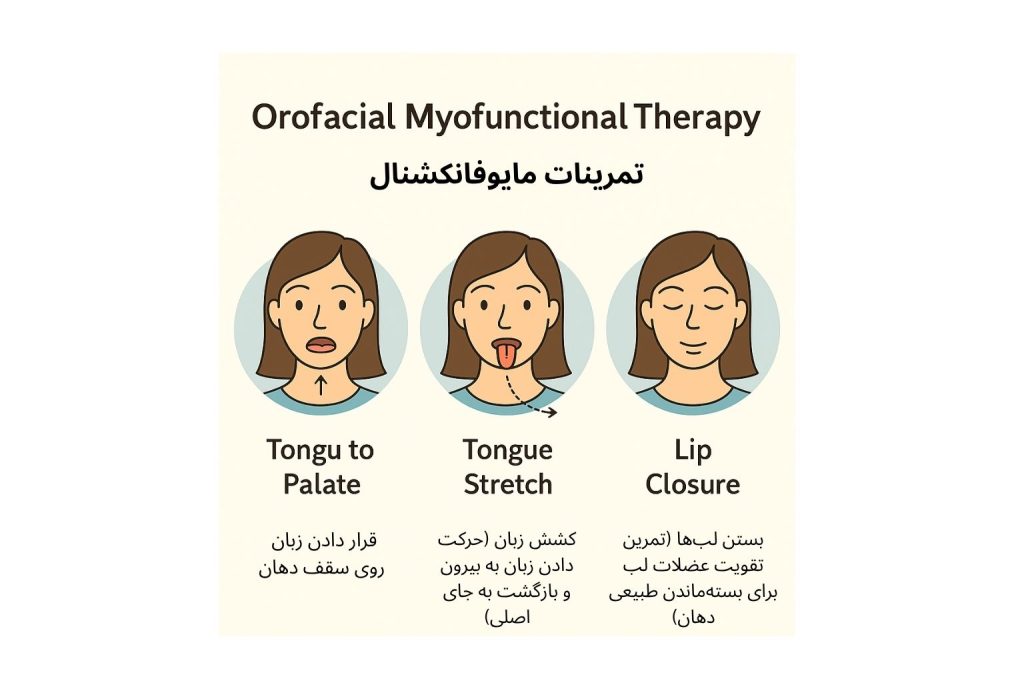

درمان معمولاً با تمرینهای مایوفانکشنال (Orofacial Myofunctional Therapy) یا استفاده از ابزارهای اصلاح عادت (Habit Breakers) همراه است.

۲. تمرینهای مایوفانکشنال (Orofacial Myofunctional Therapy)

در بیماران مبتلا به فشار زبان یا عادات بلع غیرطبیعی، تمرینهای مخصوصی برای تقویت عضلات زبان و دهان انجام میشود.

این تمرینها به بیمار کمک میکنند تا الگوی بلع طبیعی را دوباره یاد بگیرد و زبان در هنگام استراحت در محل درست (روی سقف دهان و پشت دندانهای قدامی) قرار گیرد.

تمرینها معمولاً روزانه و تحت نظر متخصص یا گفتاردرمانگر انجام میشوند و در کنار ارتودنسی، پایداری درمان را افزایش میدهند.

- انجام تمرینهای مایوفانکشنال جهت اصلاح الگوی زبان و عضلات دهان